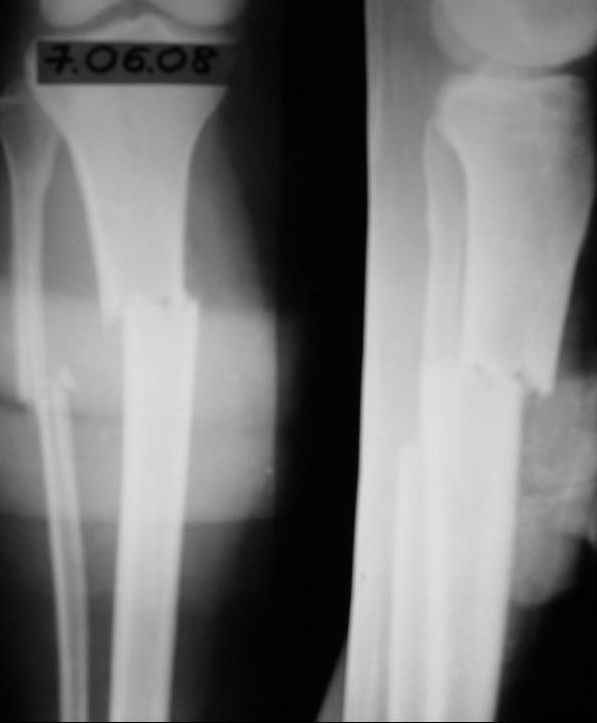

История следующая: женщина (медработник)сбита машиной 7.06.08 - о.перелом обоих костей голени в/3 со смещением. В ПДО ПХО раны,вытяжение за пяточную кость. После заживления раны 20.06.08 выполнен остеосинтез блокирующем стержнем. в течение первого месяца после травмы сохранялась субфебрильная температура на фоне приема антибиотиков. Затем температура стабилизировалась.Б-ая как положено ходила в гипсе на костылях. На контрольных рентгенограммах консолидация не достигалась, иммобилизация продлевалась. Пациентка на себе опробовала все препараты костной регенерации. В марте удален один из фиксирующих винтов. На сегодняшний день идет 11 мес. после травмы. Решается вопрос о инвалидности. Буду благодарен за предложения по дальнейшему ведению больной. Операция?